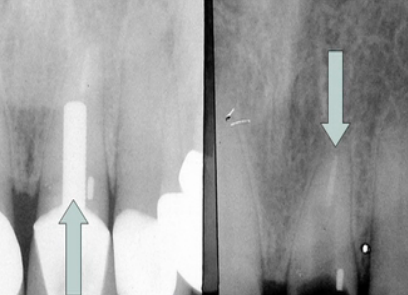

Step 2: Reduce tooth structure

With a bur, prep the tooth until it’s 0.5 mm below the bone. It may be helpful to probe to the bone and look at where the tooth is positioned relative to the bone. You can then prep the inside of the tooth and thin the walls out, allowing you to chip away parts of the tooth as opposed to grinding down the teeth and gingiva.